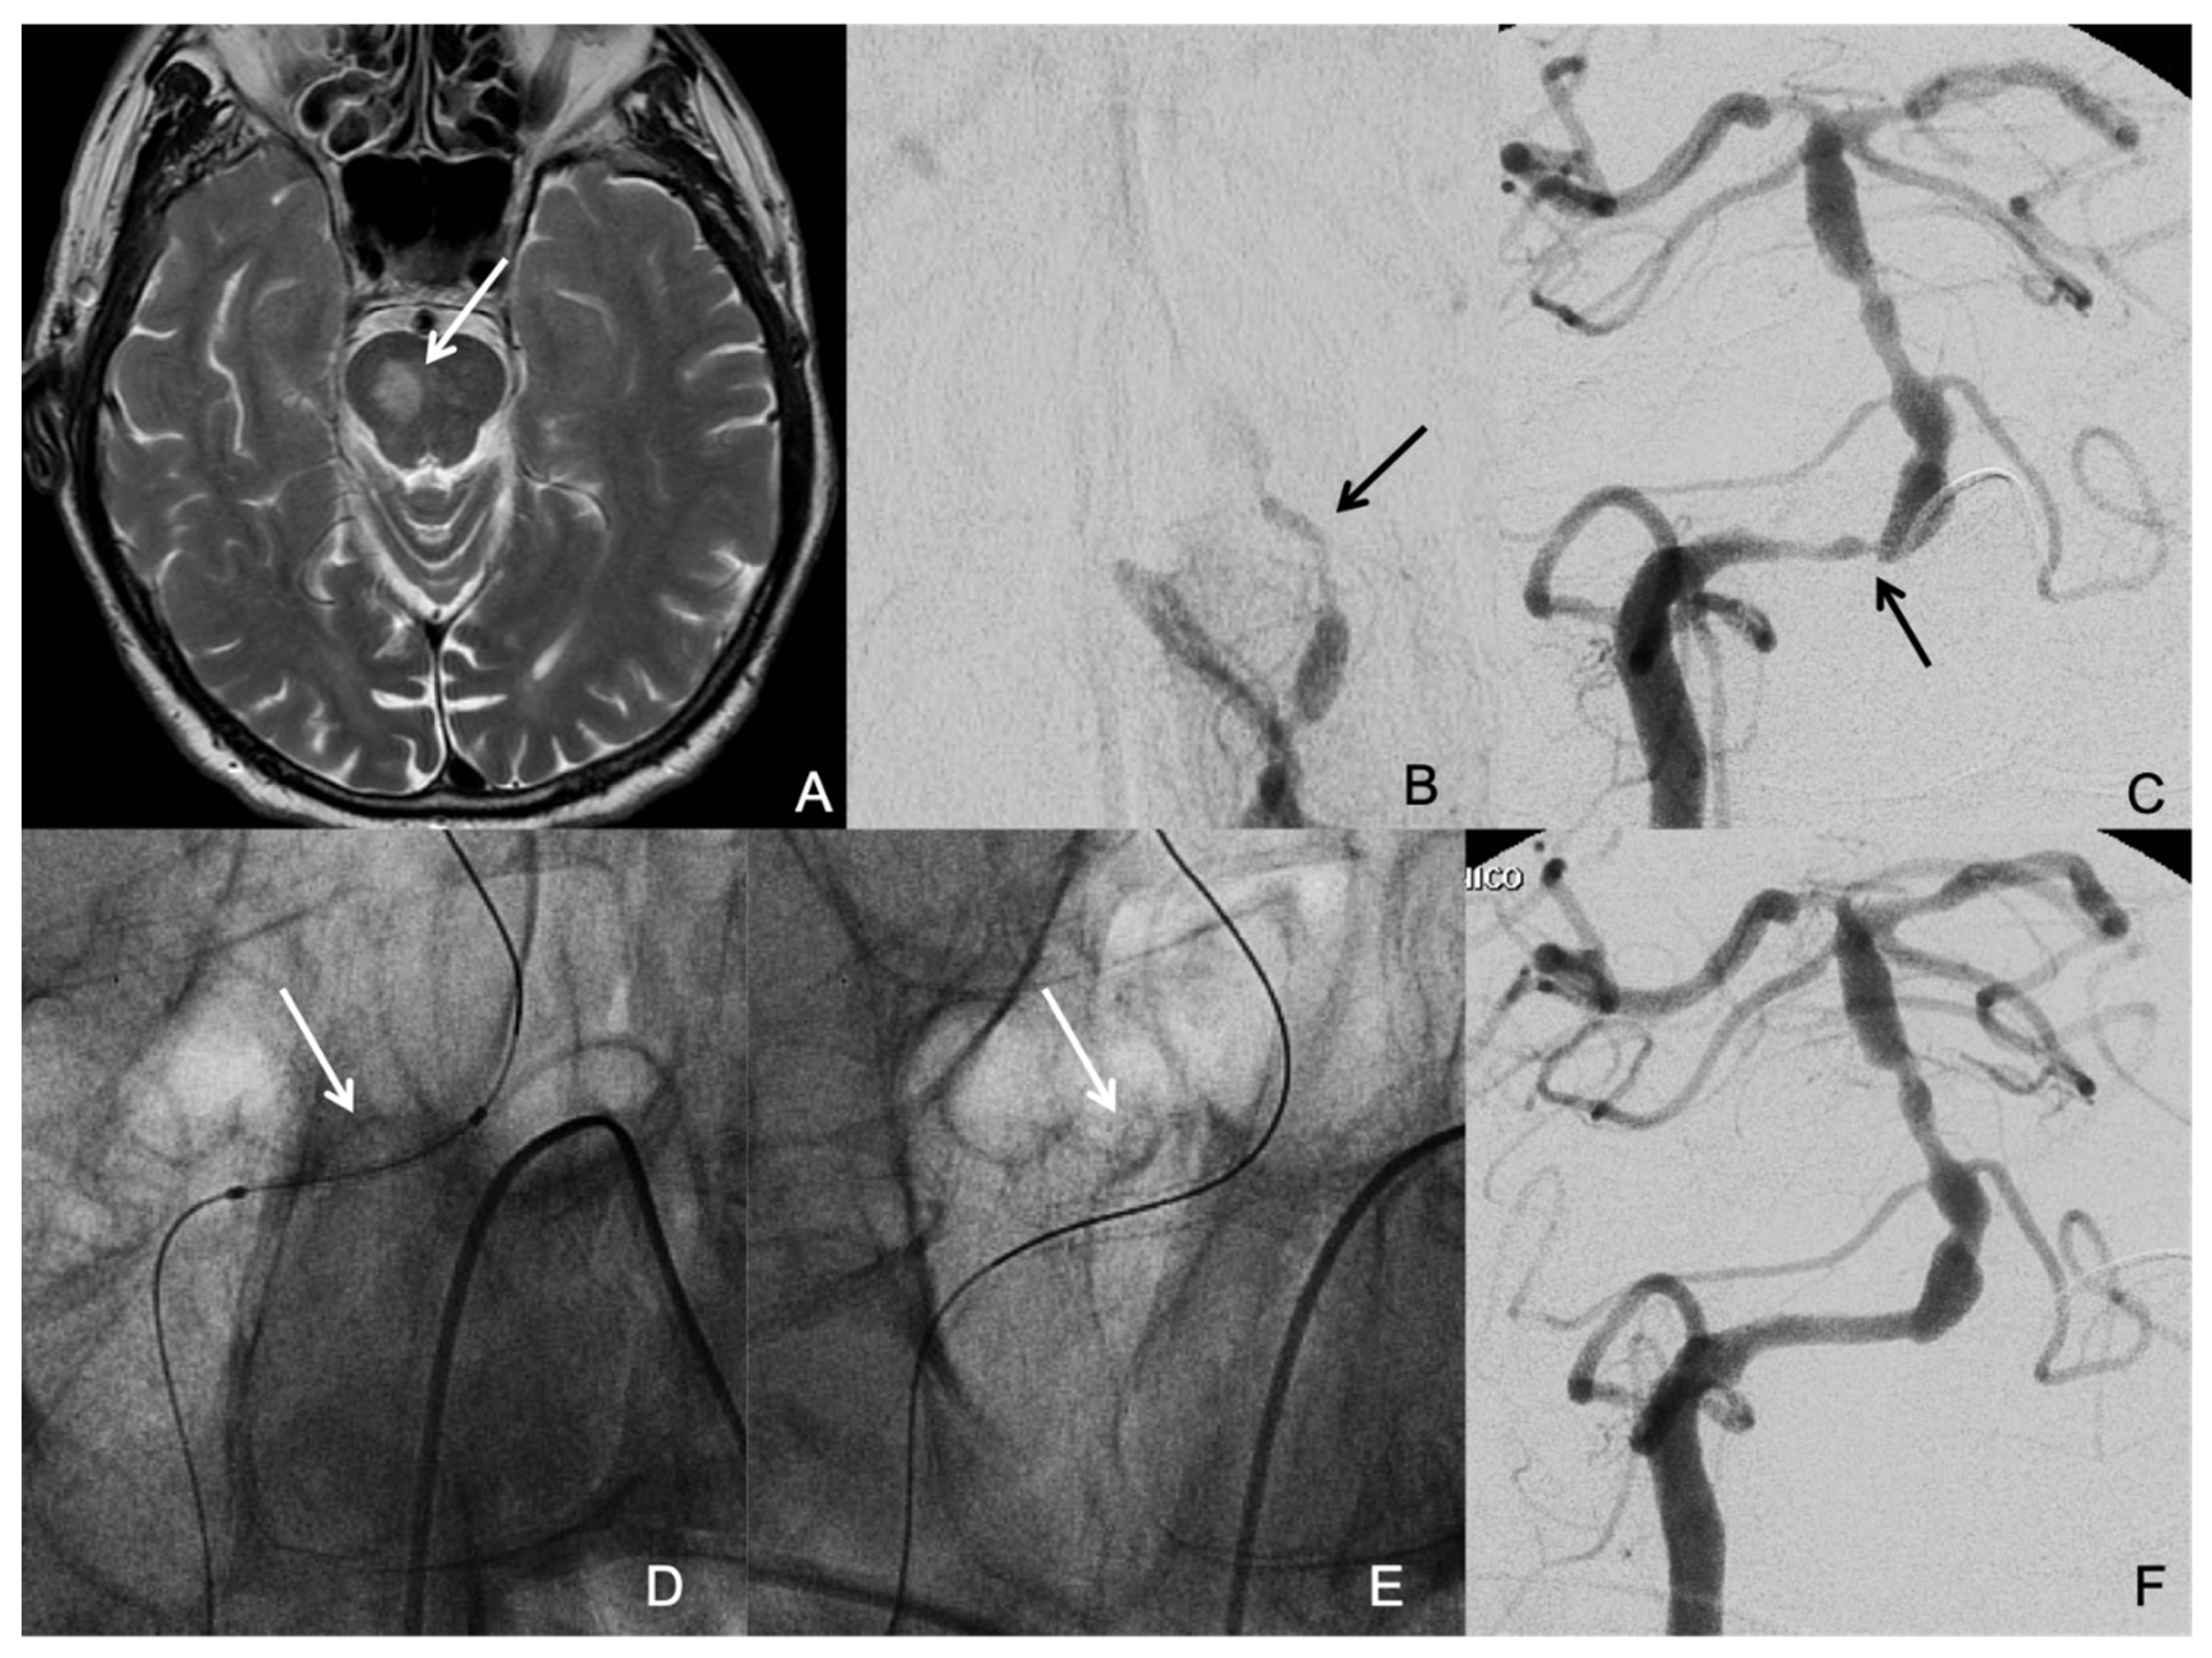

3.2. Procedure Characteristics